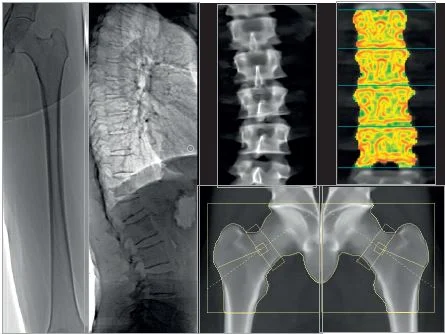

L’Ostéodensitométrie (DMO) est l’examen standard et le plus fiable pour mesurer la Densité Minérale Osseuse. Il utilise une très faible dose de rayons X pour évaluer la solidité de l’os, principalement au niveau du col du fémur et des vertèbres lombaires. Cet examen est essentiel pour le diagnostic et le suivi de l’ostéoporose.

Vous êtes allongé(e) sur une table. L’appareil scanne lentement le fémur et le rachis.